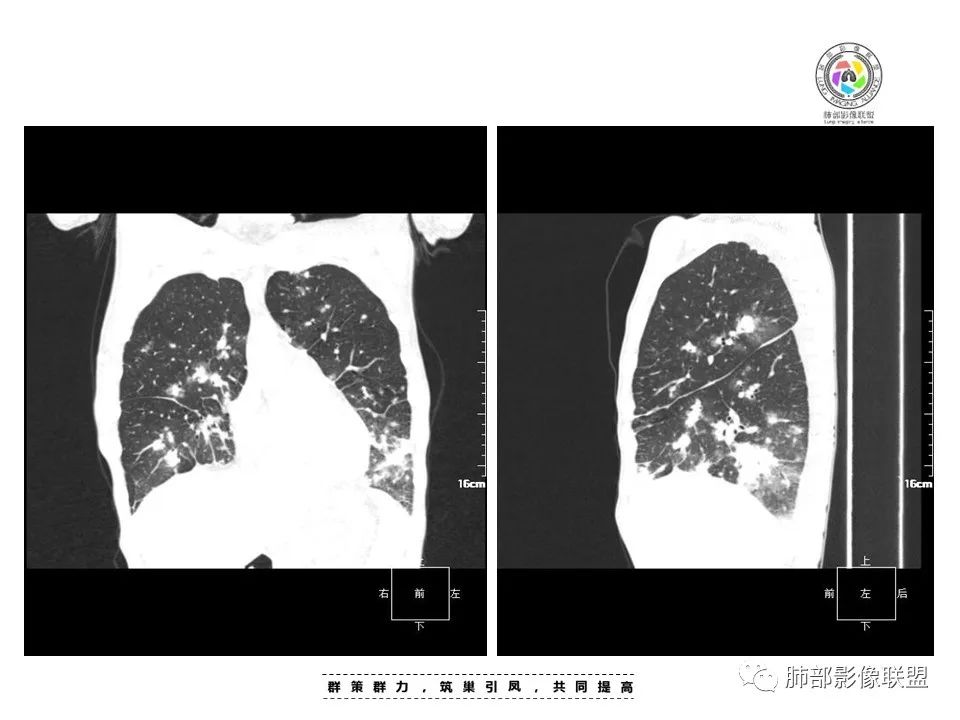

周一晚读病例:男性45岁,发热、纳差,全身散在暗紫色皮疹,结合CD4,符合HIV;肺部影像表现:两肺散在实性结节及磨玻璃密度影,实性结节伴晕征,部分沿支气管血管束分布,支气管血管束增粗,以两肺下叶为著,类似火焰征,双侧胸腔少量积液;首先考虑卡波西肉瘤,鉴别淋巴瘤增值性病变,淋巴瘤样肉芽肿/淋巴瘤,最后挂上马尔尼菲青霉菌病。

中年男性,发热、全身散在暗紫色丘疹,查CD4+T细胞64个/ul,临床信息提示AIDS并发卡波西肉瘤;CT提示双肺多发实性结节影及毛玻璃结节,部分呈点晕征,右上肺大姐姐边缘膨隆、分叶伴晕;双下肺结节沿支气管血管束分布,中轴间质增粗,部分支气管堵塞,叶间裂结节状增厚,部分结节胸膜下分布,可疑局部小叶间隔增厚,肺部病变呈淋巴分布特点,结合临床肺部病变考虑肺卡波西肉瘤,鉴别淋巴瘤。

两肺弥漫性性结节状、小片状及片状带晕的病灶,煎蛋征、点晕征,主要分布两肺中下叶,病灶周围小叶间隔增厚呈网格状影,部分病灶累及胸膜,伴两侧胸膜增厚。

2.本例双肺小叶间隔增厚明显,多发结节影及片状实性密度影,沿血管支气管束分布为主,两侧较为对称,病灶多环以磨玻璃晕,边界不清。

双侧胸腔少量积液。双肺门及纵隔未见明确肿大淋巴结,纵隔结构间隙模糊。

3.有学者将这种具有沿双肺支气管束分布的实性密度片影描述为“火焰征”,认为具有一定特征性,单就影像表现而言,这种影像表现也可以见于其他病损或多种病理改变的叠加。

1.结节型:两肺沿支气管血管束分布的结节影,呈火焰状或星芒状、挂果征,局部周围出血磨玻璃影(肺泡出血或水肿)。

2.支气管血管束增粗型:

肺门周围支气管壁呈“套袖样”改变。

3.肺炎渗出型:

斑片渗出影,部分融合呈“火焰样”,同时有火焰样结节,小叶间隔增厚等表现。

还可以有纵隔及腋下淋巴结增大,胸腔积液等表现。